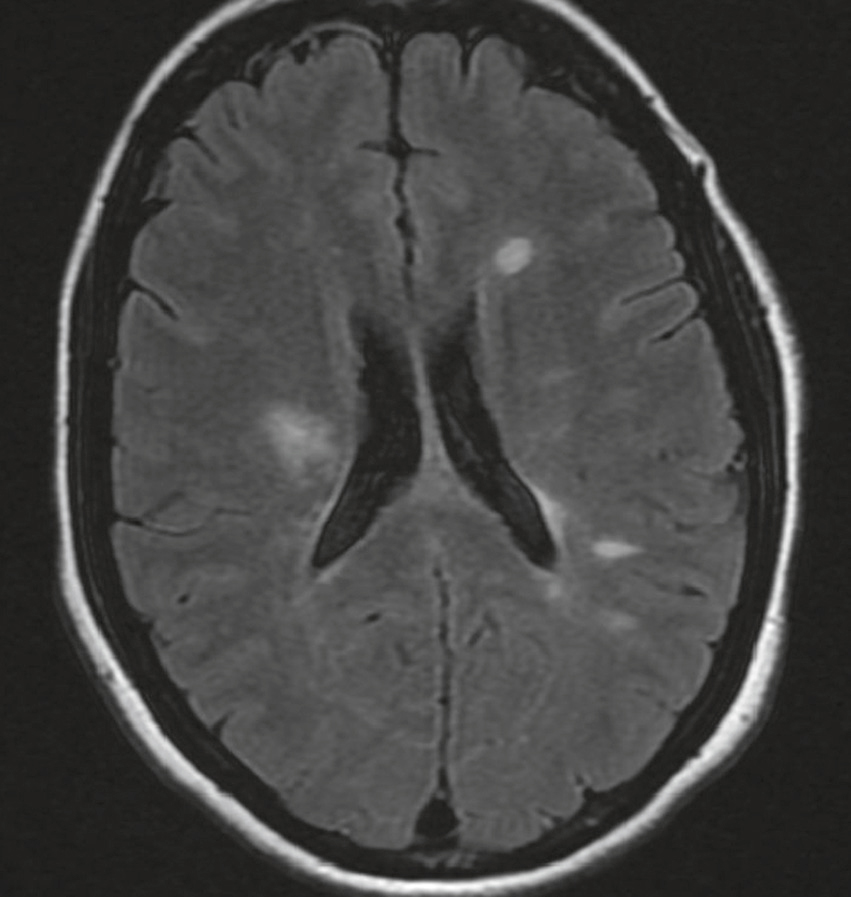

QRM 42

Une jeune femme de 30 ans présente une gêne visuelle rapportée à une ophtalmoplégie internucléaire. Une IRM est pratiquée (fig. 32.3). À propos de cette IRM, quelle(s) est (sont) la (les) proposition(s) exacte(s) ?

Des images de coupe axiale mettent en évidence les ménages de plusieurs petites hyperintensen, que le cerveau MRI conserve dans les séquences et se propage des fusées et se propage dans la matière blanche des deux têtes cérébrales, en particulier les régions périduculo- et sous-corticales. Ces hyperconcludations, bien contrôlées par rapport au tissu cérébral normal, reflètent les changements dans la myéline ou les processus inflammatoires chroniques. L'apparition et la distribution des lésions conduisent à la démultiplication de la pathologie, comme la sclérose en plaques, en particulier en l'absence d'effets de masse ou d'œdème associé.

- A IRM en séquence de diffusion

- B lésions situées dans la substance blanche hémisphérique

- C lésions évocatrices de localisation néoplasique secondaire

- D dissémination spatiale en faveur du diagnostic de sclérose en plaques

- E séquence IRM en T1 injecté nécessaire avant de retenir le diagnostic de sclérose en plaques